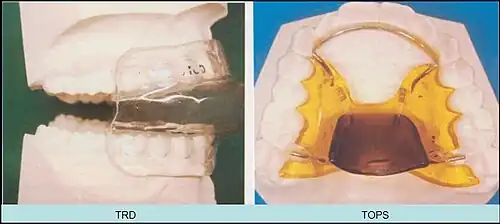

Tongue retaining device

Tongue retaining devices are devices that can be placed in a manner such that the tongue is kept in a forward position. These devices have been used for snoring and obstructive sleep apnea.[16]

Tongue retaining devices hold the tongue in place by either suction, a fixed bar, or a custom dental impression. Hybrid devices combine mandibular advancement with the tongue restraint.[17] Tongue retaining devices have not been well-received as a therapy choice since they are invasive, and the acclimation period is long.[18] The devices have shown high success rates for therapy in studies published in Behaviour Research and Therapy[19] and the Journal of Clinical Sleep Medicine.[20]